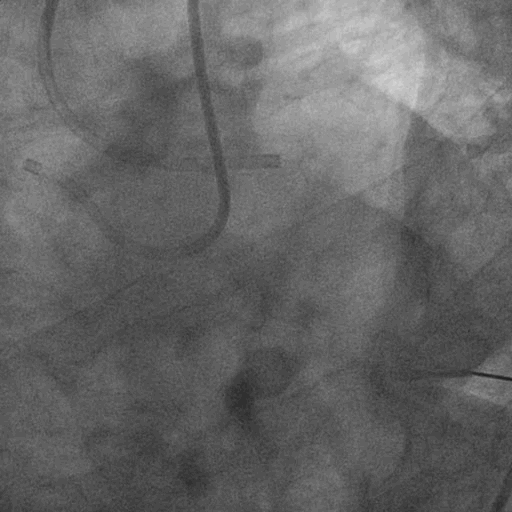

左冠造影:

右冠造影:

双侧造影: